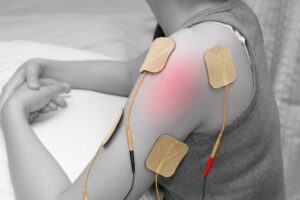

استفاده از دستگاه های پیشرفته مانند الکتروتراپی و اولتراسوند نیز به کاهش درد و بهبود جریان خون کمک میکند. فیزیوتراپی نه تنها علائم را کاهش میدهد، بلکه با اصلاح الگوهای حرکتی از بازگشت مجدد گرفتگی جلوگیری میکند.

استفاده از تجهیزات مدرن در فیزیوتراپی تاثیر درمان را افزایش میدهد. دستگاه های الکتروتراپی با تحریک کنترل شده عضلات، به کاهش درد و اسپاسم کمک میکنند.

اولتراسوند درمانی نیز با افزایش عمق نفوذ گرما، جریان خون را بهبود میبخشد. بهره گیری از این تجهیزات در کلینیک فیزیوتراپی خانه سلامت، روند بهبودی را تسریع میکند.